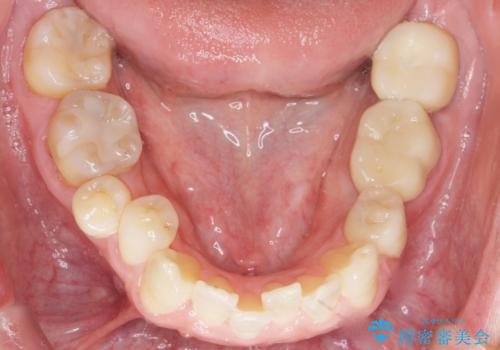

- 下の奥歯が内側に生えていることを主訴に来院された患者様です。

精査したところ、左下の小臼歯(左下5)が舌側転位しており、また隣の歯の詰め物は欠け虫歯になっていました。